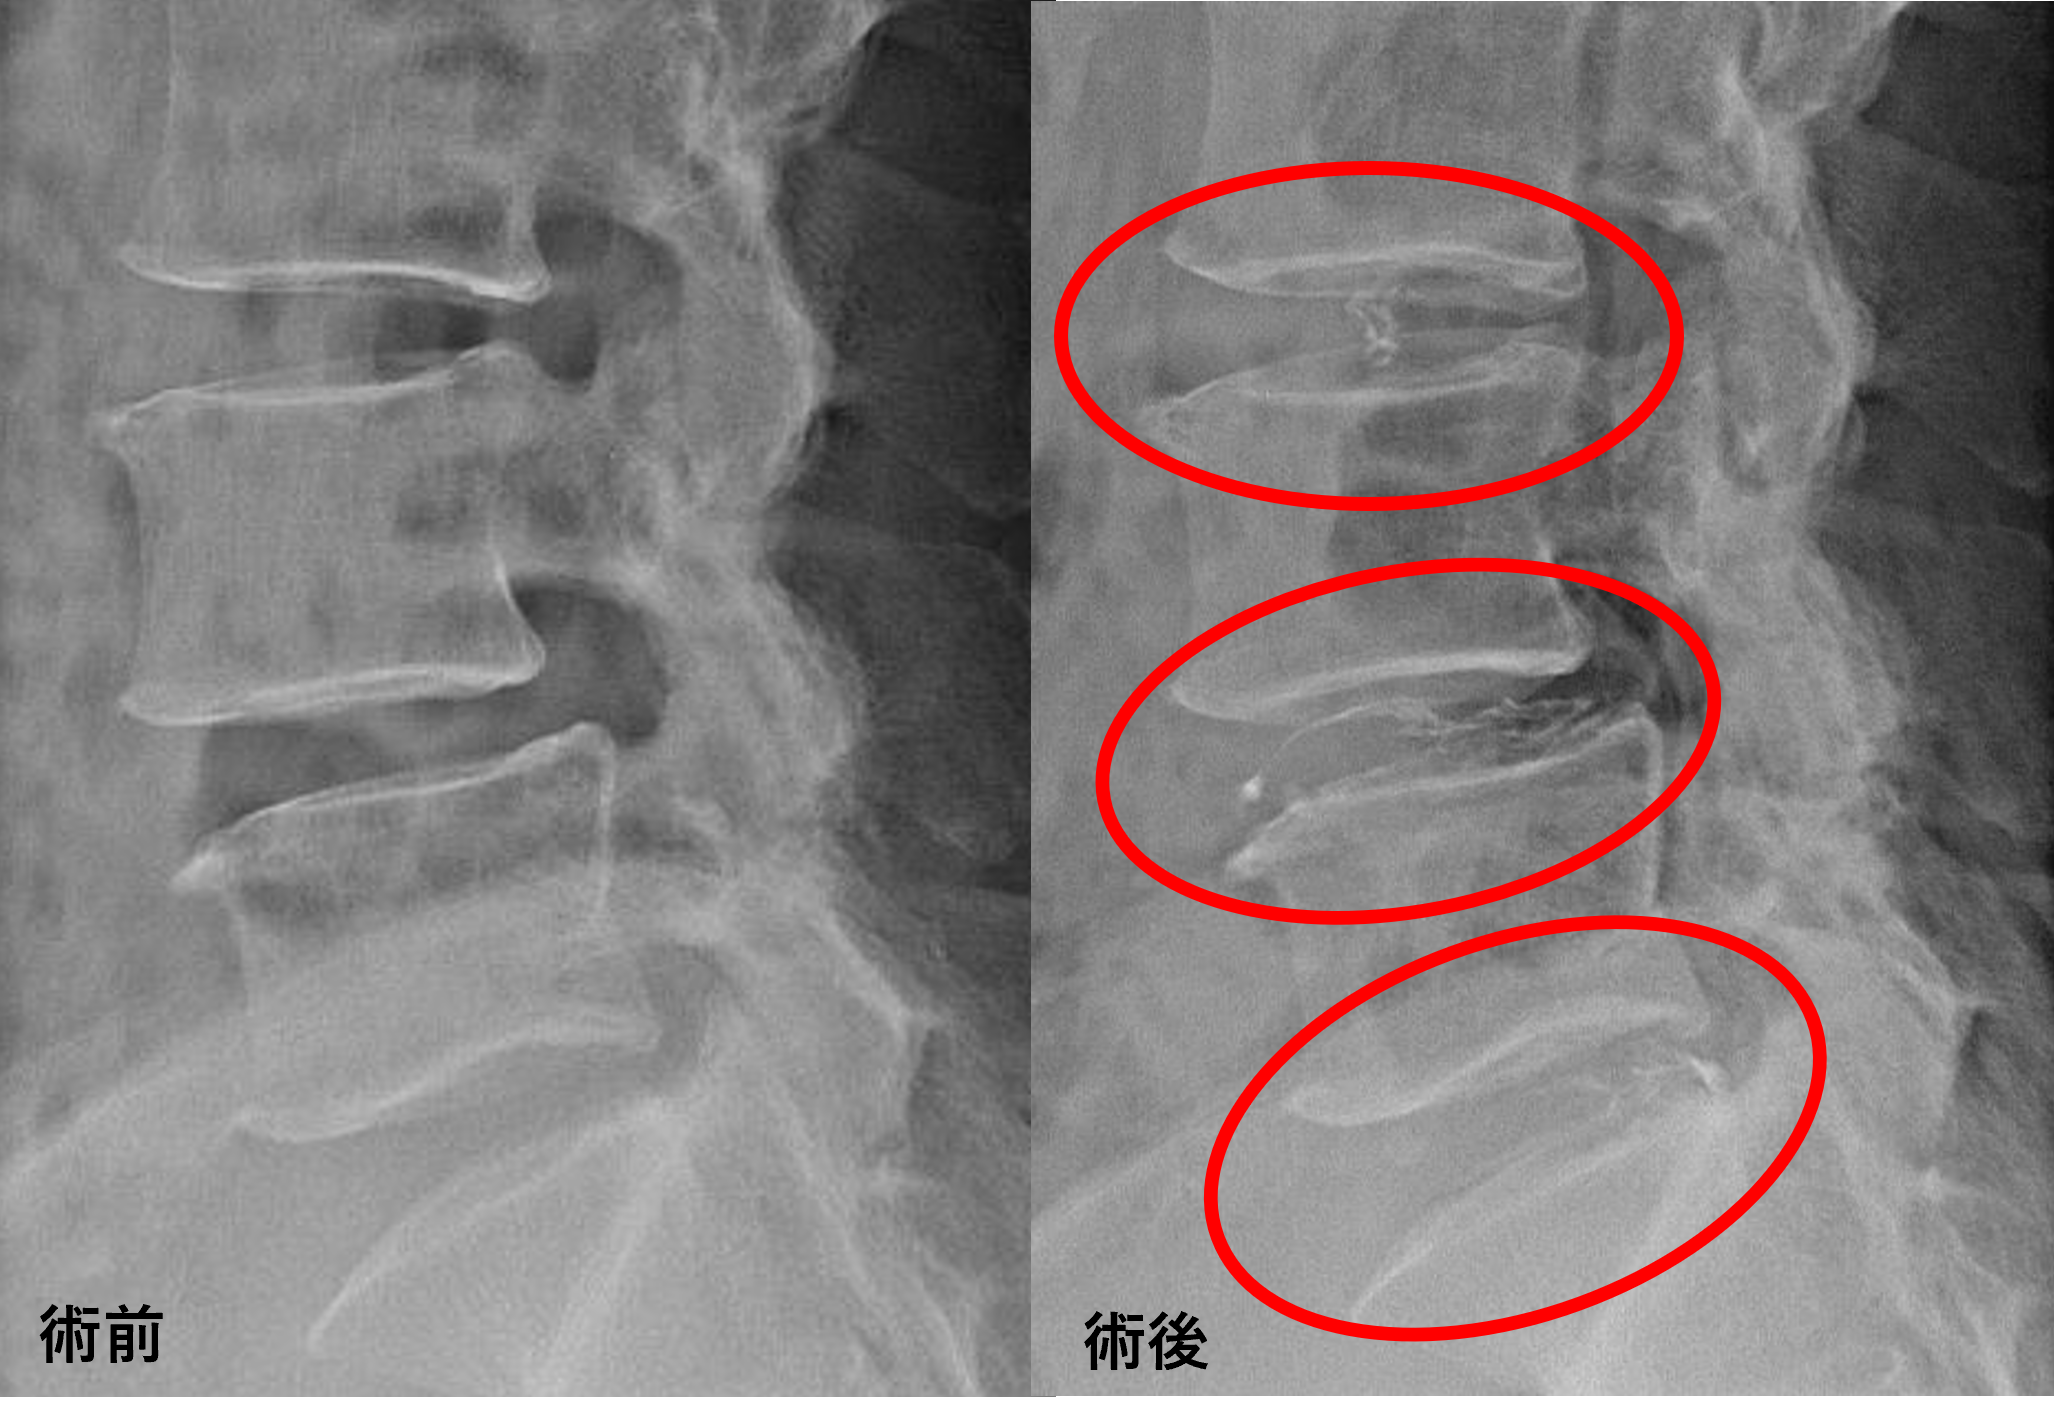

画像及び所見について

• L3/4、5/s – 椎間板変性、膨隆

• L4/5 – 椎間板変性、膨隆、変性すべり

以上のことが画像上認められました。

L3/4、4/5、5/sの椎間板所見による脊柱管の圧排が、症状の原因の可能性が高い。

患者様と相談の元、L3/4、4/5、5/sにセルゲル法を施行